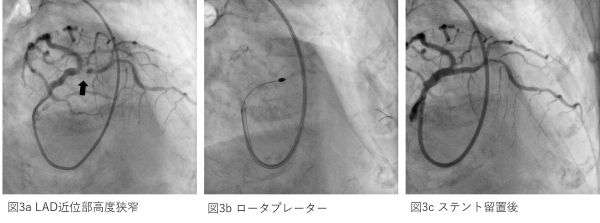

図1 冠動脈複雑病変というのは分岐部病変、慢性完全閉塞病変(閉塞してから6か月以上経過したもの)や石灰化病変などがあります。特に石灰化病変(動脈硬化が進行し病変が石のように固くなった病態)に対しては通常のバルーンによる拡張やステント治療は困難なことがあります。このような病変に対しては高速回転冠動脈アテレクトミー:Rotablator (ロータブレーター)が必要となってきます(図2)。

これはわかりやすく言えば、硬い病変を削るドリルのようなもので、先端にダイアモンドチップを埋め込んだバーといわれるドリルを1分間に14~18万回転で回転させて硬い病変を削ります。その結果、バルーンによる拡張やステント治療をさせやすくすることができます。このRotablator (ロータブレーター)を使用するには施設基準がありますが、当院においては2020年4月から使用することができるようになりました(2020年4月現在は下関エリアでは唯一です)。

図2 図3の症例は70歳代の女性の患者様で労作時の胸痛を主訴に心臓カテーテル検査を行いました。冠動脈造影検査では左冠動脈前下行枝(LAD)入口部に石灰化を伴う高度狭窄を認めました(図3a)。バルーンは不通過であったので拡張困難でしたが、ロータブレーターで病変を削ることにより(図3b)、ステント留置をすることができ(図3c)、狭窄を解除することができました。